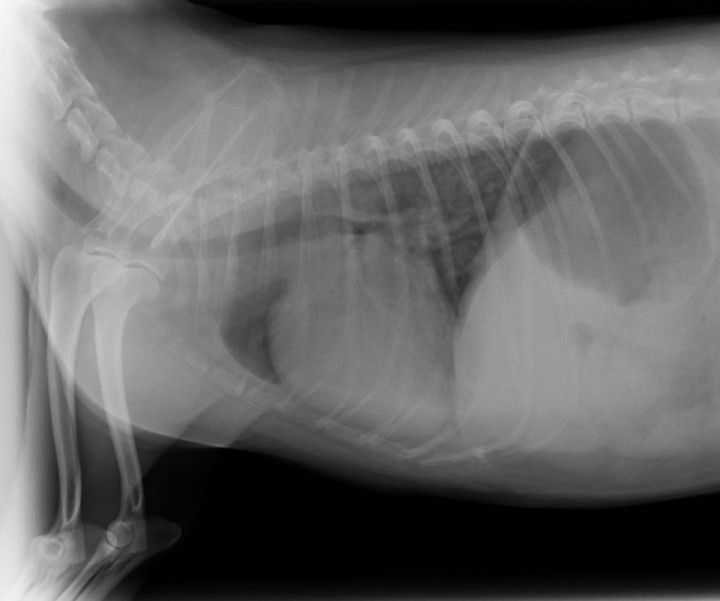

El paciente muestra disnea de tipo mixto y taquipnea (52 respiraciones por minuto). El estudio radiográfico del tórax revela la existencia de un patrón alveolar en zona perihiliar hacia lóbulos caudales compatible con edema pulmonar de tipo cardiogénico y un tamaño en el eje corte de 12 cuerpos vertebrales[ Buchanan JW, Bucheler J: Vertebral scale system to measure canine heart size in radiograms. J Am Vet Med Assoc 1995;206:194. [PubMed] ] (rango normal 9,7 +/- 0,3) (Fig. 2). Asimismo, el estudio ecocardiográfico muestra una sobrecarga de volumen ventricular izquierda, sin aumento del tamaño atrial, pero con dilatación de las venas pulmonares (Fig. 3). Las medidas ecocardiográficas muestran un aumento de la fracción de acortamiento (Fig. 4) y de eyección (VE), un ratio aorta aurícula izquierda correcto (Ratio ao/ai) y aumento del índice volumétrico telediastólico final (EDVI) (Tabla 1). No se observan alteraciones estructurales congénitas ni adquiridas.

<p>Presencia de patrón alveolar en región perihiliar, compatible con edema pulmonar cardiogénico.</p>

Figura 2

Presencia de patrón alveolar en región perihiliar, compatible con edema pulmonar cardiogénico.